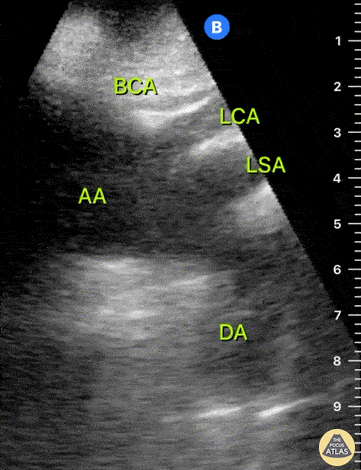

Aorta - Normal Aortic Arch - Suprasternal View

This clip represents a normal suprasternal view. The brachiocephalic artery (BCA), left carotid artery (LCA) and left subclavian artery (LSA) emerge from the aortic arch (AA). The left subclavian artery (LSA) marks the division between the proximal thoracic aorta and the distal descending aorta (DA). Dr. Felipe Urriola P., Emergency Unit, Puerto Aysen Hospital, Chilean Patagonia.